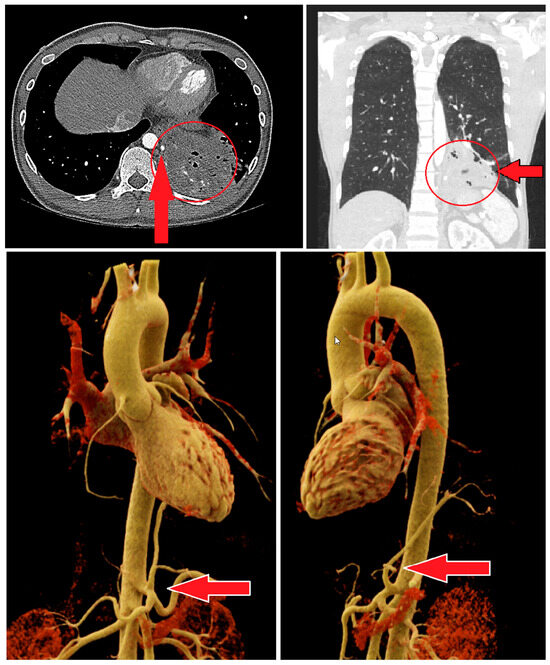

Due to a suspected case of pulmonary tuberculosis, prompted by a radiologically identified cavitary lesion in the left lower lobe, a chest CT scan was conducted. The imaging revealed the presence of a pulmonary sequestration located in the left lower lobe (segments 9–10). This sequestration exhibited multiple cystic components and gas inclusions. The venous drainage of the sequestrum was through peripheral segmental pulmonary artery branches, while the systemic arterial supply originated from a branch of the celiac trunk or the left gastric artery (Figure 1).

Figure 1. The red arrow indicates the arterial supply to the sequestration of the left lower lobe, which originates from the celiac trunk. The red circle highlights the extent of the sequestration.